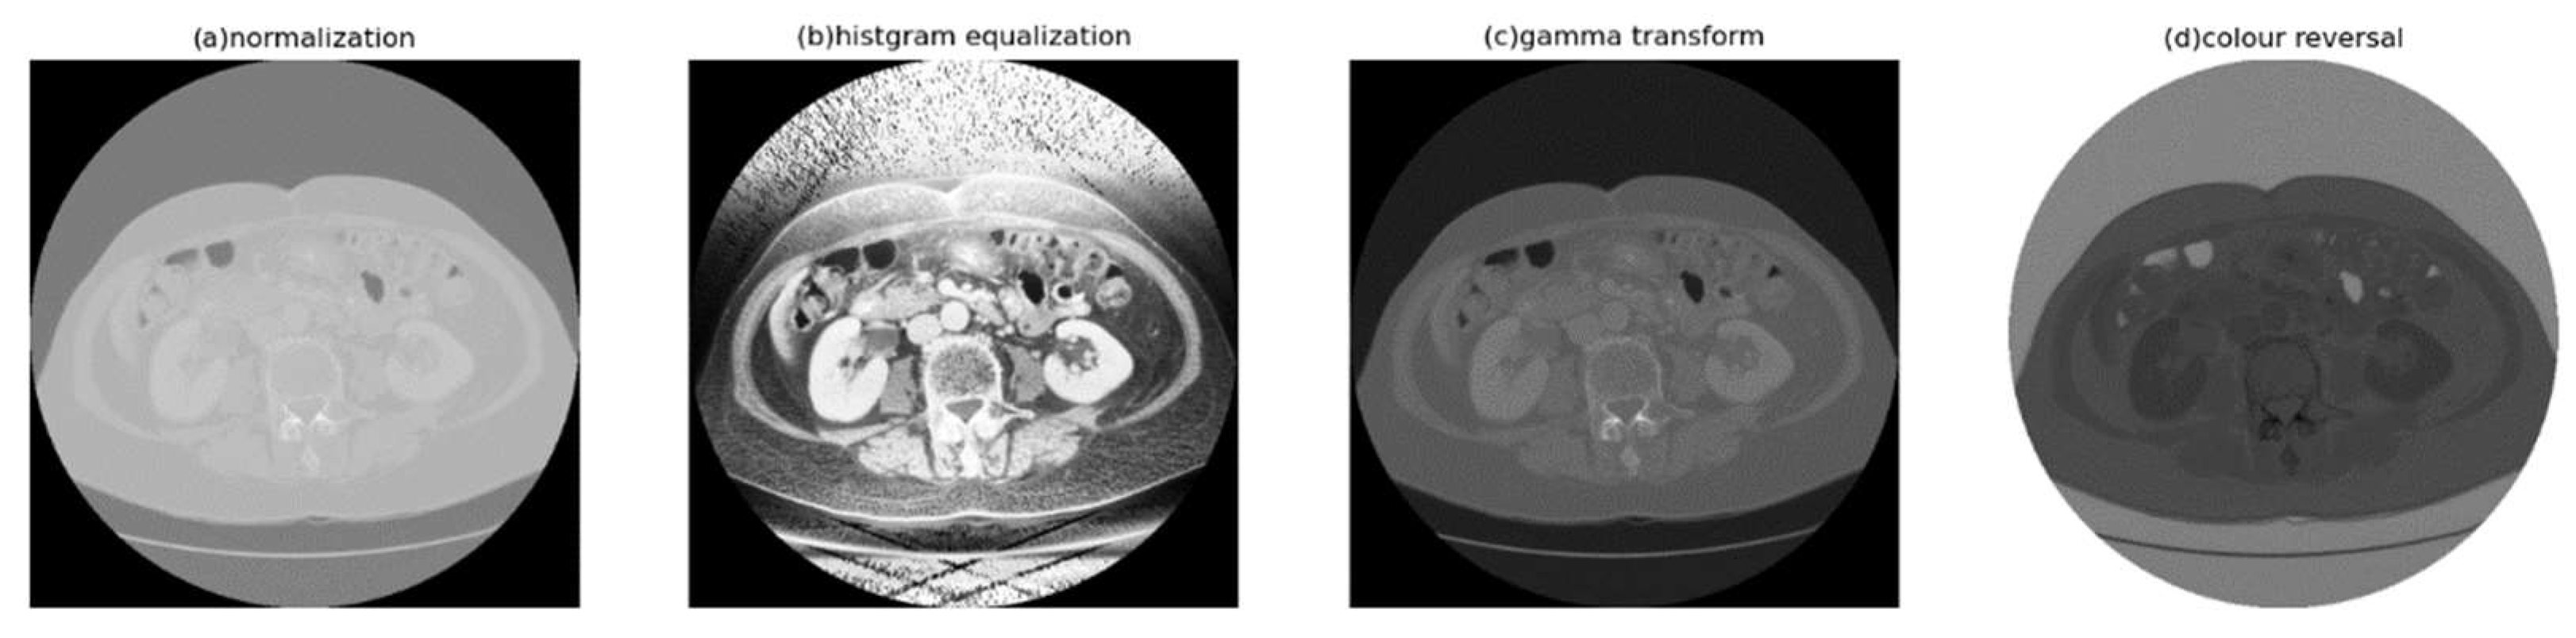

- Digital image enhancement strategies for medical image features: Medical images often contain a high level of noise and details hidden in low-intensity regions. To address this, anisotropic diffusion filters are used for denoising, and histogram equalization is employed to enhance the texture and details of medical images globally. Additionally, the fusion of window level and window width adjustment techniques specific to medical images is applied to target the regions of interest within the image. These strategies aim to achieve global enhancement of medical images while highlighting the desired targets.

3.3. Histogram Equalization

3.4. Window Adjustment